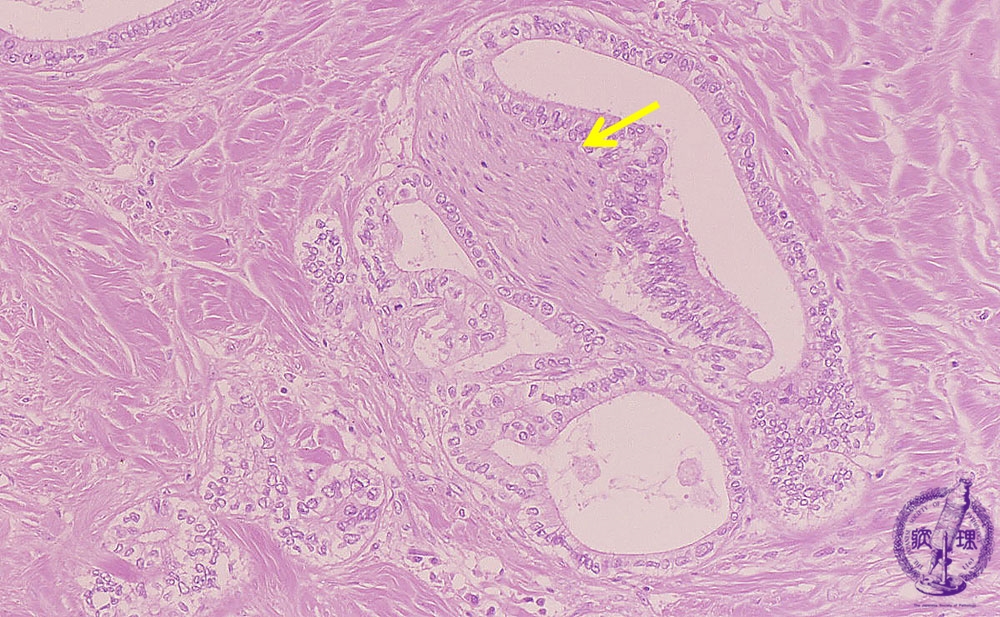

- ★(13)Intrahepatic bile duct cancer (adenocarcinoma)

Microscopic image (HE stain, intermediate power): Neuronal invasion (yellow arrow) by tubular adenocarcinoma is seen.